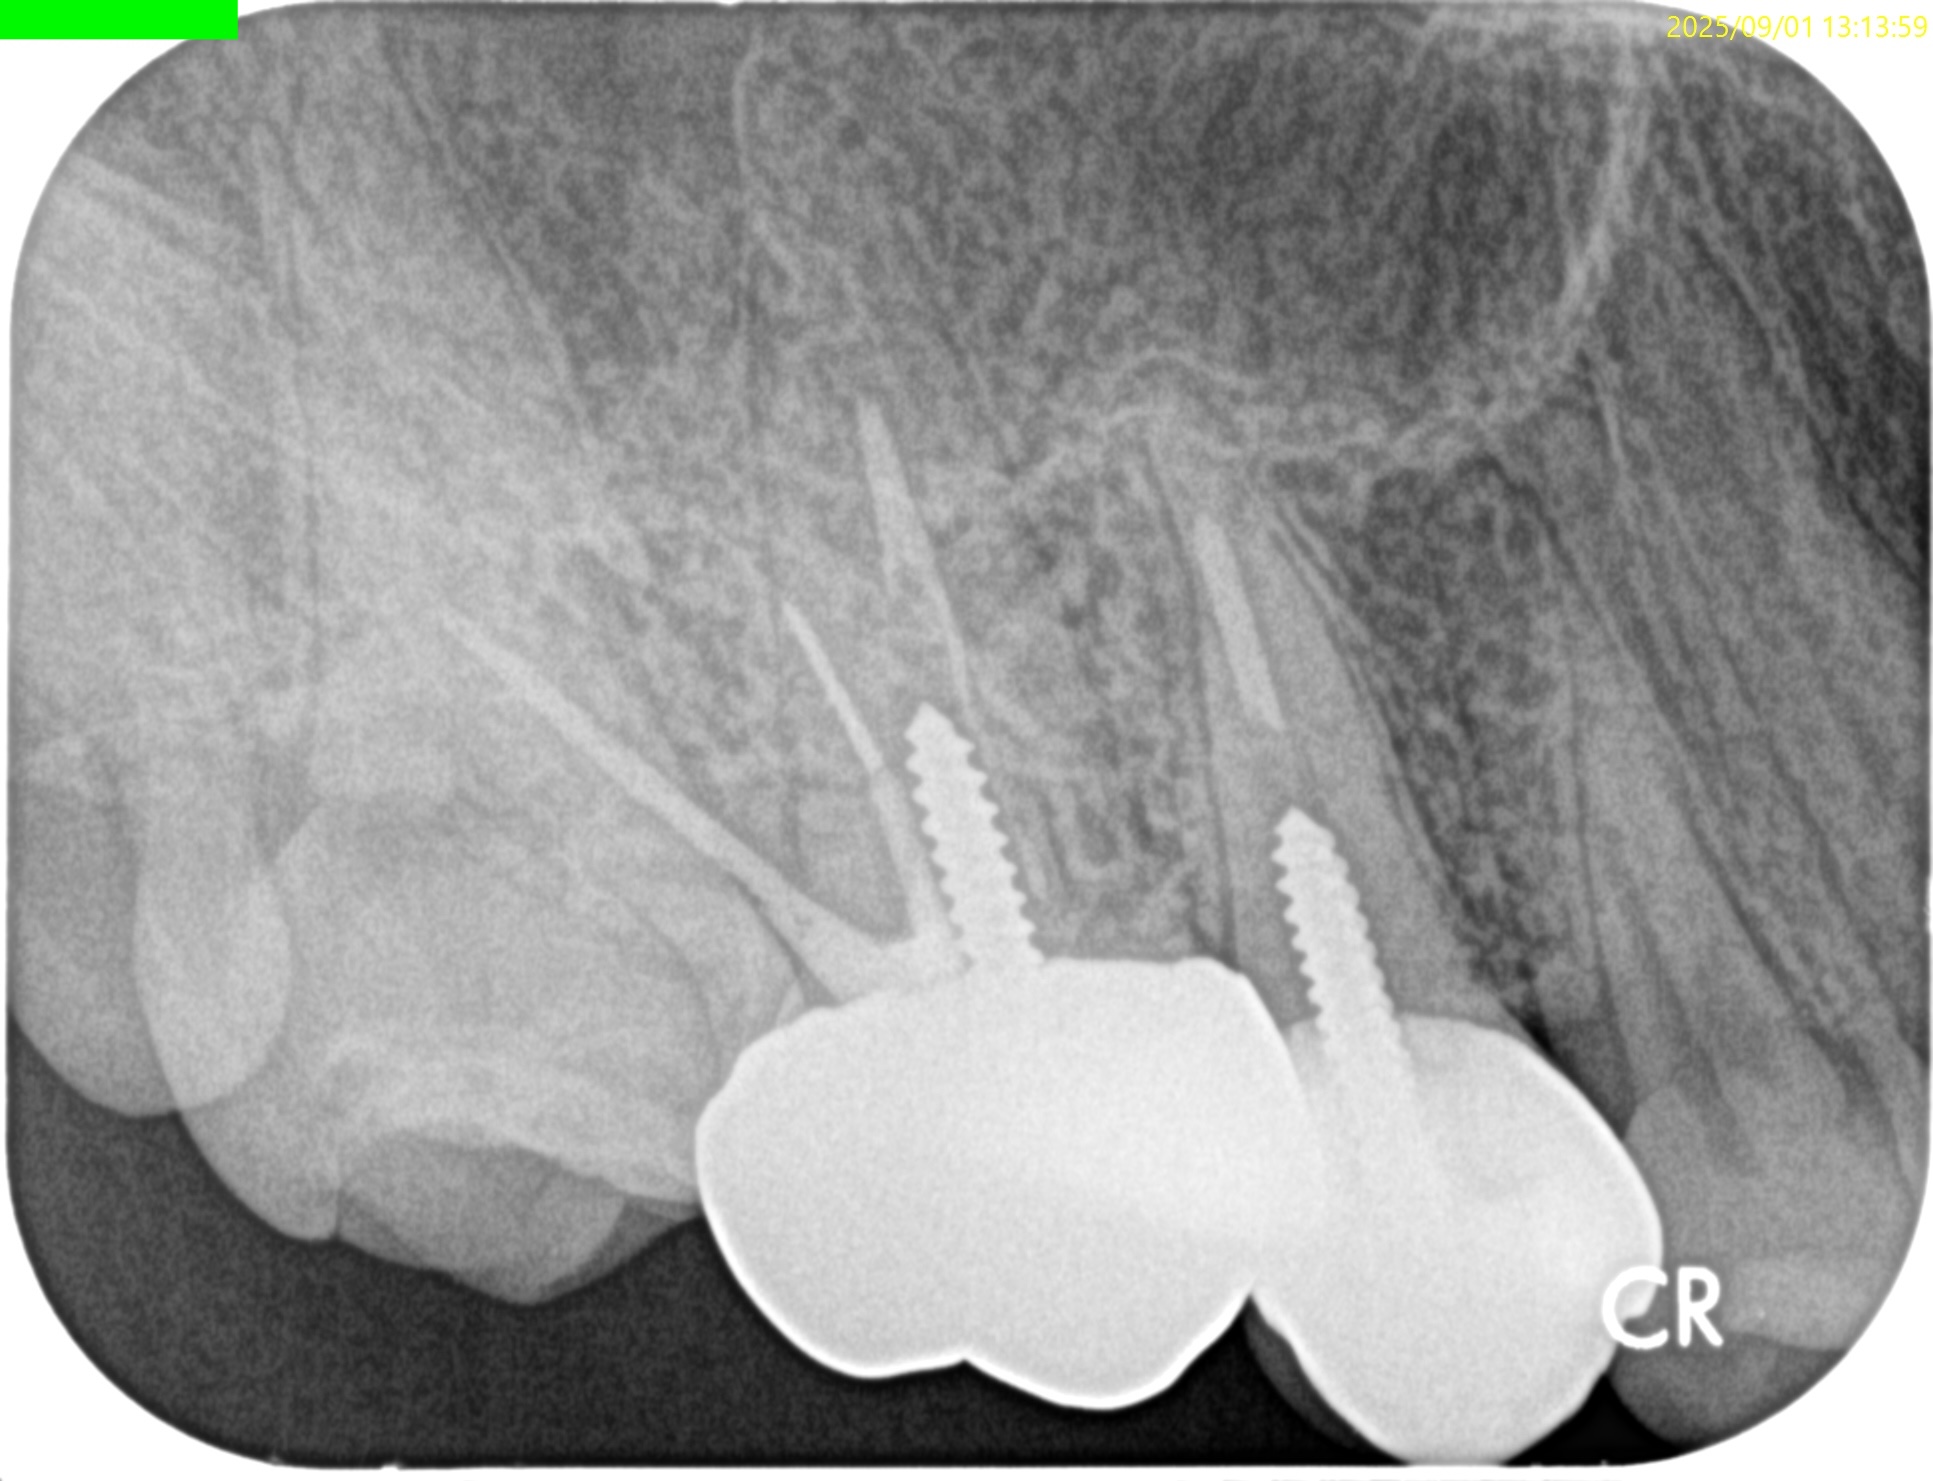

PA(2025.9.1)

#3のMBにはFileが折れ込んでいる。

#4はP根管が未着手だ。